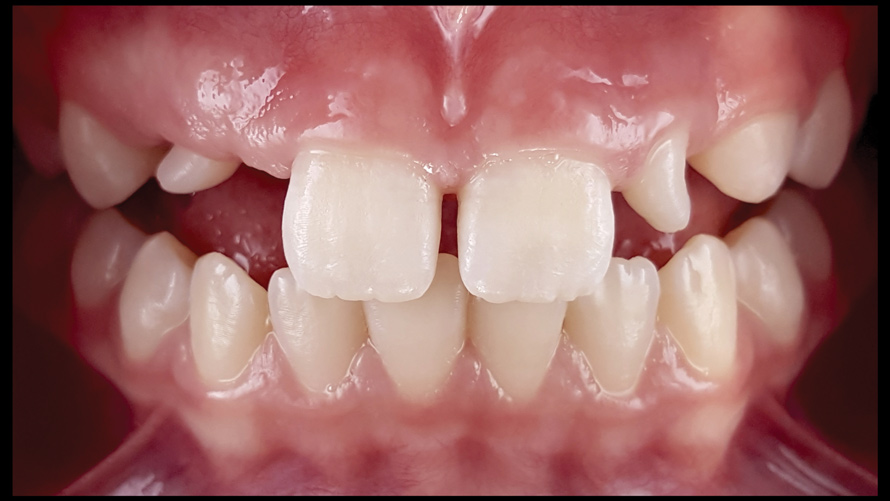

One of the main advantages that smartphone cameras have over DSLR cameras is that nearly everyone is already very familiar with the technology; therefore, the incorporation of these devices into everyday practice does not require learning a new and unfamiliar skill set. The task of producing a series of high-quality clinical photographs for routine examinations (Figure 8), esthetic treatment planning (Figure 9 through Figure 11), or specialty care (Figure 12 and Figure 13) can be delegated with confidence to any staff member during the patient's initial office visit and will generally require less than 5 minutes of time to complete. When a DSLR camera is used, evaluation of the intraoral images either takes place on the small viewfinder built into the camera or necessitates the physical removal of the memory card from the camera to downloaded the images onto a computer for review. An added bonus of smartphone dental photography is that the phone's screen now replaces the much smaller viewfinder of a DSLR camera and provides the clinician with the ability to view and zoom into the patient images on a 5- to 6-inch, high-definition display.

(8.) Routine case photograph taken with a smartphone and an EALS device.

Figure 8

(9.) Preoperative esthetic case documentation using a smartphone and an EALS device.

Figure 9

(10.) Preoperative esthetic case documentation using a smartphone and an EALS device.

Figure 10

(11.) Preoperative esthetic case documentation using a smartphone and an EALS device.

Figure 11

(12.) Intraoral photographs taken with a smartphone and an EALS device for orthodontic evaluation.

Figure 12

(13.) Intraoral photographs taken with a smartphone and an EALS device for orthodontic evaluation.

Figure 13